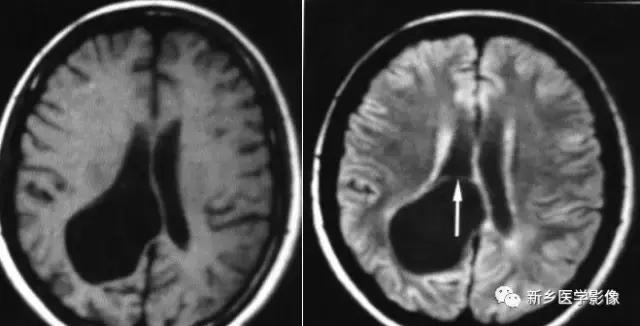

(3)无脑回和巨脑回

无脑回和巨脑回是一组因神经元移行异常所致的脑回发育异常。巨脑回也称平滑脑。巨脑回指有部分脑回存在,这些脑回异常增大增宽.脑沟变浅。巨脑回主要位于额、颞部。无脑回上要位于顶、枕部。

临床上,无脑回和巨脑回畸形患儿均表现有小头畸形和轻微的面部异常,完全无脑回畸形常在两岁前死亡.不完全无脑回畸形存活常能长期。

CT和MR均能够很好显示无脑回和巨脑回畸,表现为大脑半球表面几乎呈光滑状,仅可见少数宽阔、粗大、平坦的脑回,脑沟缺如.脑灰质增厚,脑白质变薄,灰白质分界面异常平滑,见不到白质向灰质内伸入的现象。常见透明中隔腔存在.侧脑室扩大,蛛网膜下腔增宽。